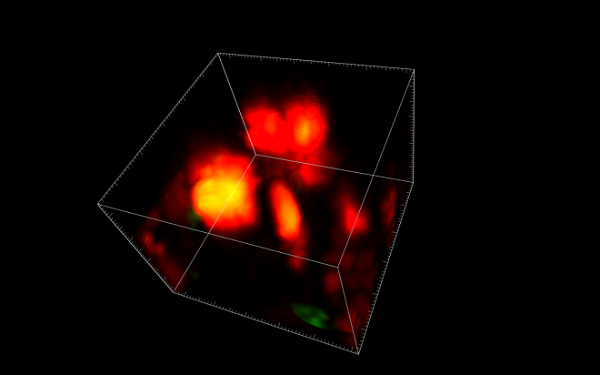

Использовав технологию интравитальной визуализации, учёные смогли заглянуть глубоко внутрь живой костной ткани, где они обнаружили, что остеокласты не просто умирают после выполнения своей работы, но делятся на более мелкие клетки, прежде чем переродиться. Заинтересовавшись находкой, исследователи использовали секвенирование РНК для установления её генетического профиля.

«Профиль генов, которые были включены в этих клетках, был действительно интересным - в то время как многие гены также экспрессировались остеокластами, некоторые были уникальными, – рассказал автор исследования доктор Вэн Хуа Ху. – Это, вместе с доказательствами новых процессов повторного слияния, наблюдаемых с помощью интравитальной визуализации, убедило нас в том, что мы открыли новый тип клеток, который мы назвали остеоморфами, в честь Могучих рейнджеров-морфинов».

Дальнейшие эксперименты показали, что 17 из 40 обнаруженных генов остеоморфов влияют на размер и прочность костей, будучи связанными с вариантами генов, которые отвечают за минеральную плотность ткани и могут провоцировать развитие таких состояний, как дисплазия скелета. В будущем открытие планируется использовать для изучения новых подходов к лечению остеопороза и других скелетных заболеваний.

Фото: Dr Michelle McDonald